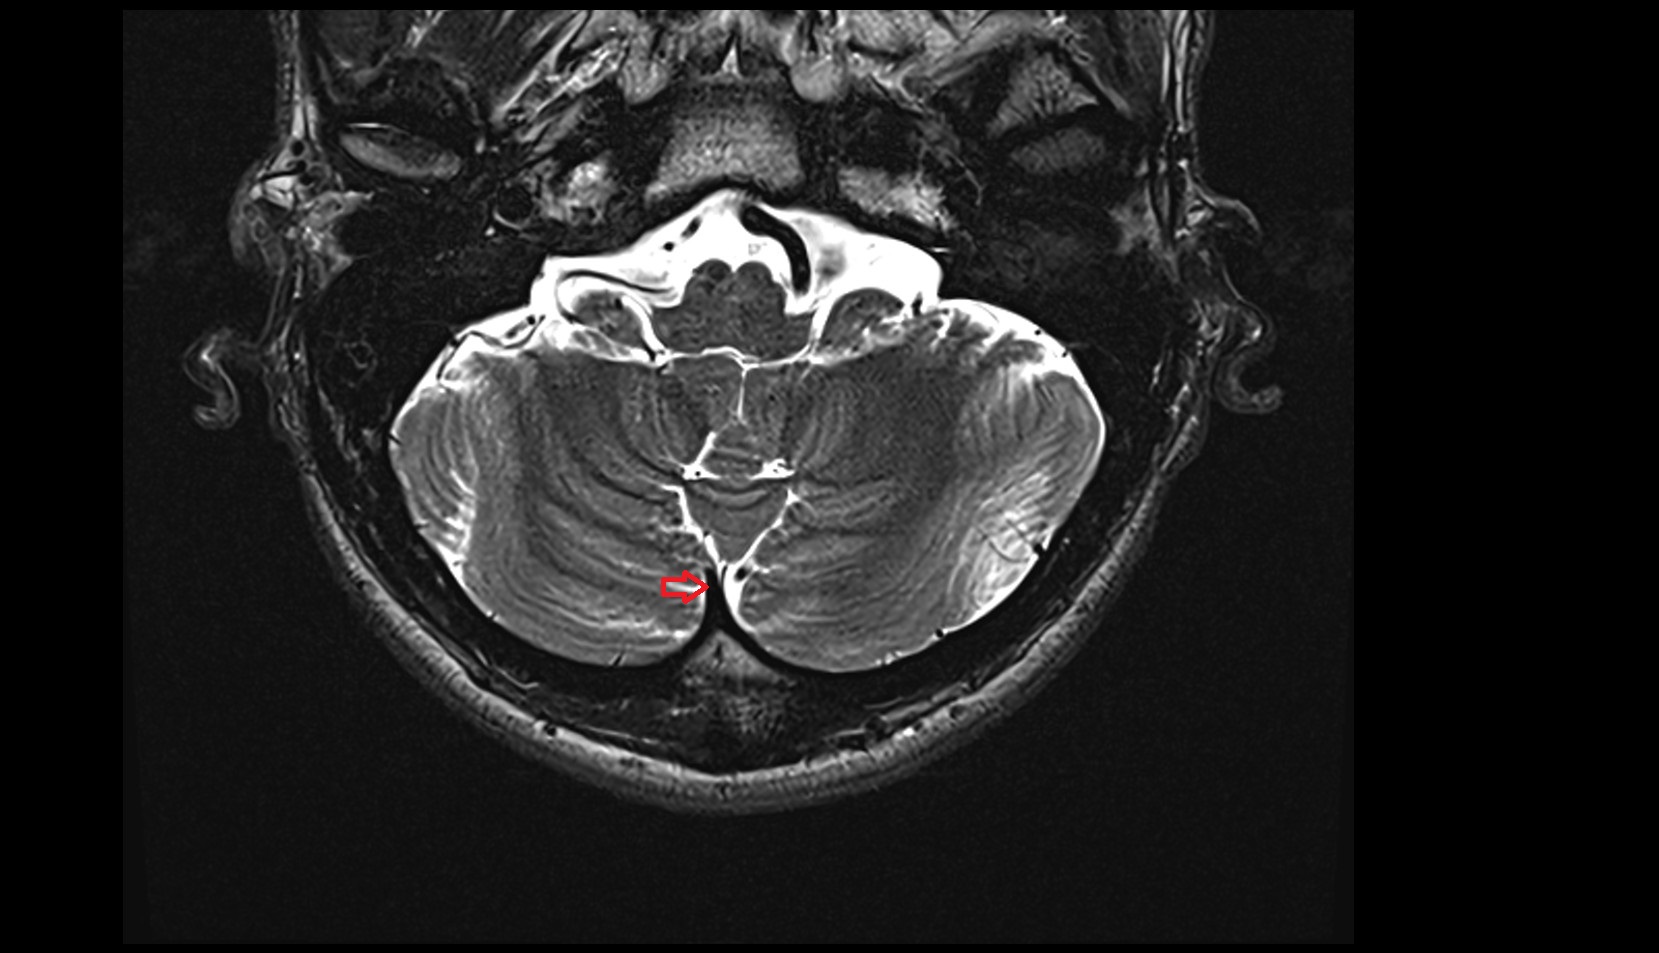

- Cerebellar tonsil (H IX)

- Tonsil of cerebellum

- Flocculus